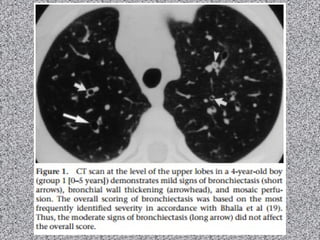

Fibrose cística: imagem

TACR de tórax:

Bronquiectasias (principal achado):

Pode ser dos 3 tipos; geralmente bilaterais;

Predomina nos lobos superiores;

Espessamento brônquico;

Impactação mucoide pode ocorrer;

Nódulos centrolobulares;

Árvore em brotamento;

Consolidações;

Lesões císticas ou bolhosas nos ápices;

Linfonodomegalias hilar e mediastinal

Anormalidades pleurais (derrame e/ou espessamento)

Fibrose Cística

Homem de 37 anos com tosse crônica e dispneia progressiva